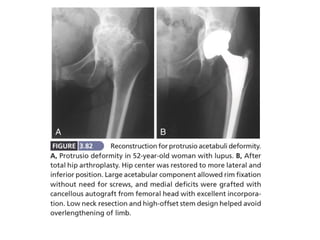

PROTRUSIO ACETABULI

The principles of reconstruction of a protrusion deformity are

as follows:

(1) the hip center must be placed in an anatomic location to

restore proper joint biomechanics;

(2) the intact peripheral rim of the acetabulum should be used

to support the acetabular component;

(3) the remaining cavitary and segmental defects in the medial

wall must be reconstructed, preferably with bone grafting

PROTRUSIO ACETABULI The principlesof reconstruction of a protrusion deformity are as follows: (1) the hip center must be placed in an anatomic location to restore proper joint biomechanics; (2) the intact peripheral rim of the acetabulum should be used to support the acetabular component; (3) the remaining cavitary and segmental defects in the medial wall must be reconstructed, preferably with bone grafting